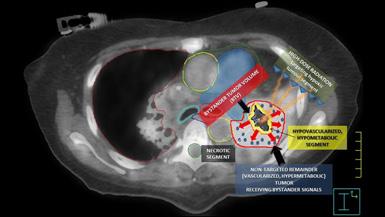

Figura 1. Leziune decelată colonoscopic la 25 cm de OA Figura 2: Îngroșare parietală asimetrică la nivelul joncțiunii recto-sigmoidiene Figura 3. Adenocarcinom moderat diferențiat, cu arhitectură tubulară